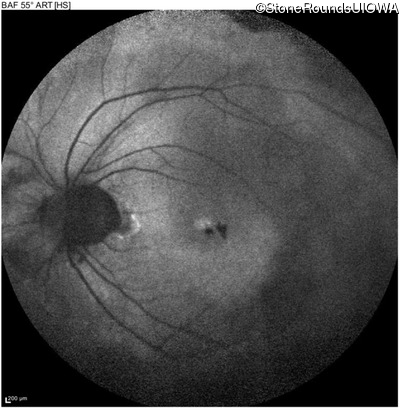

Age at visit: 47 years

OD OS

This 47 year old woman began wearing glasses at age 5 and had cataract surgery at age 32. At that time her doctor noticed a retinal abnormality.